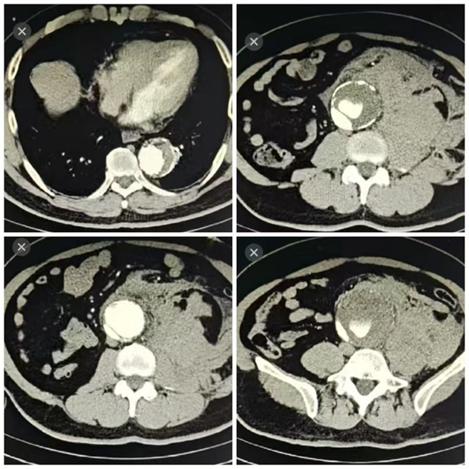

11月15日凌晨1时许,该患者因突发腰背部剧烈疼痛到我院紧急就诊。据了解,该患者10年前曾因胸主动脉夹层接受胸主动脉腔内修复术,院外增强CT检查提示胸腹主动脉瘤,病变最危险部位的血管直径已扩张至7.5cm,且血液正持续从破口渗出,这颗藏于患者体内的“不定时炸弹”一旦彻底破裂,将引发致命性大出血,患者生命危在旦夕。

面对挑战,赖应龙教授团队邀请首都医科大学朱俊明教授团队胡海瓯教授,联合我院麻醉科、手术中心、体外循环及重症监护团队参与救治,并进行了详尽的术前模拟与预案推演,为患者量身定制了周密的手术方案。在12个小时的紧张手术中,多学科团队采用了顶尖的“深低温停循环”技术,为精细操作创造了宝贵的时间窗口,病变的主动脉被成功替换为人工血管,所有重要分支血管均实现精准吻合。术后,患者生命体征平稳转入该科重症监护室进一步治疗,经过10余天的精准救治与精心护理,患者饮食睡眠、肝功能、肾功能、心脏功能及凝血功能显著好转,顺利出院。